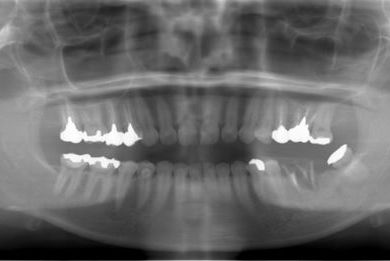

抜歯即日スピードインプラント治療+セラミック治療+歯肉歯槽骨整形術

| 治療方針 | 左下欠損部と保存不能の歯を抜歯し、インプラント治療にて機能的・審美的回復を行う。 | ||||||||||||||||||||||||||||||||

| 治療内容 | インプラント2本(抜歯即日スピードインプラント)、ハイブリッドセラミッククラウン2本、歯肉歯槽骨整形術 | ||||||||||||||||||||||||||||||||

| 総治療費 | 488,250円 | ||||||||||||||||||||||||||||||||

| 治療期間 | 1年4ヶ月 |